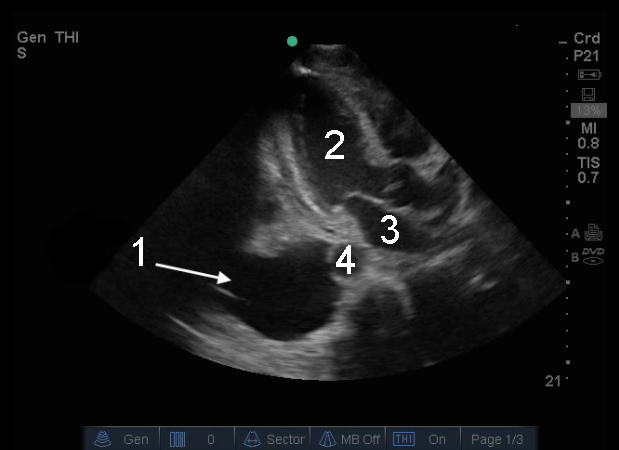

Bild 2: Herz, parasternale lange Achse (PLAX), Pleuraflüssigkeit

1. Rechter Pleuraerguss (Flüssigkeit)

2. Linker Ventrikel (LV)

3. Linkes Atrium (LA)

4. Aorta (Ao)